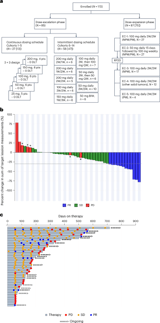

Most patients in the trial had previously undergone immunotherapy and chemotherapy, yet VT3989 demonstrated significant responses, including partial tumor regressions and stable disease, with an 86% disease control rate among treated mesothelioma patients.

The ongoing phase 1/2 trial evaluates VT3989's efficacy and safety, showing good tolerability and notable antitumor activity, particularly in heavily pretreated patients with extensive prior therapies.

Overall, the preliminary data supports VT3989 as a promising targeted therapy across solid tumors, with ongoing research exploring combination therapies and biomarker-driven patient selection.